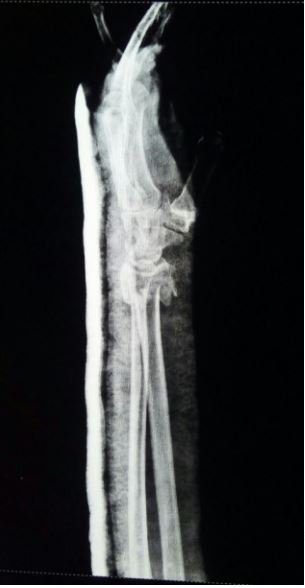

My father have accident on 21-jan and POP is done in FMH emergency,Now seeing the scan please suggest what the further treatment can be done as he is hearth patient and have nose surgery too due to same accident

Thank you for asking. The radiographs of your father are showing that distal radius height, volar tilt and angulation are NOT in acceptable range. The recommended options are close reduction under image intensifier using wires and than a cast for 4 to 6 weeks. Otherwise open reduction and internal fixation using locking plates.

i have seen your father's xrays. I agree with first answer that Position of fracture should be improved for best outcome.

If your father is high risk for general anaesthesia, its not a problem. wrist surgery can be safely performed under Local or Regional Anaesthesia.